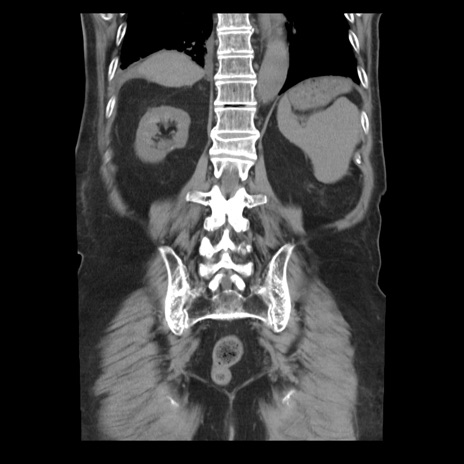

横断像

【症例】70歳代男性

【主訴】腹痛

【現病歴】肝硬変・肝細胞癌にてかかりつけの方。約9時間前に食後より腹痛出現。症状が徐々に増悪し、嘔吐出現したため来院。

【既往歴】肝硬変、肝細胞癌(RFA、TACE後)

【身体所見】意識清明、表情苦悶様、BT 36℃、BP 129/78mmHg、P 88bpm、SpO2 97%(RA)、右上腹部から心窩部にかけて圧痛あり、反跳痛なし、筋性防御あり。

【データ】WBC 5800、CRP 0.16